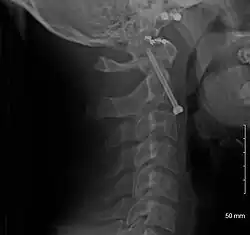

-

A fracture of the base of the dens as seen on plain X-ray -

A fracture of the base of the dens as seen on CT -